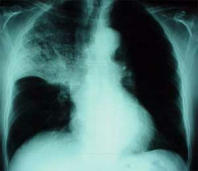

Pneumonia, x-ray photo

Blood group AB has - like blood group A - a chronic problem of mucus which provokes always a vulnerability for infection diseases: sinusitis, bronchitis, and pneumonia etc.

Example here is an x-ray photo with a pneumonia in the upper half of the right part of the lung.

-- pneumonia, x-ray photo: http://www.doktor.ch/krankheiten/lungenentzuendung.html